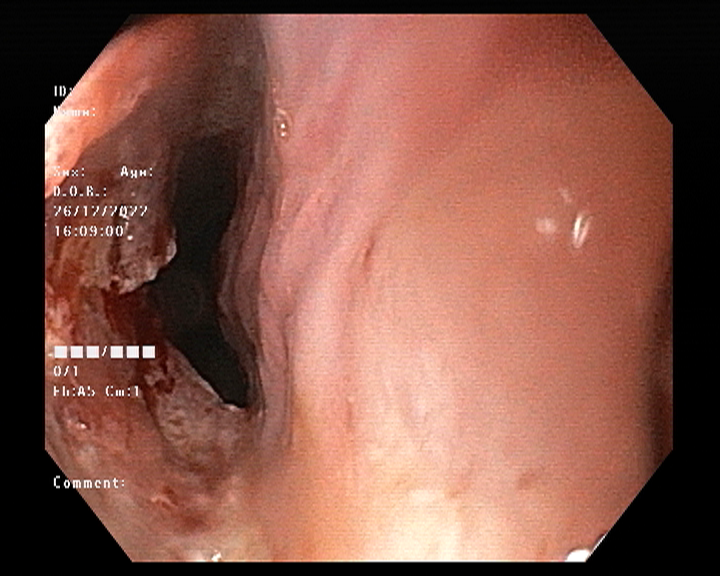

Endoscopy and colonoscopy are safe and accurate procedures used to directly examine the digestive tract and detect the root cause of chronic acidity, GERD, abdominal pain, bleeding, and bowel irregularities. These minimally invasive tests help identify ulcers, inflammation, infections, polyps, strictures, and early cancerous changes.

At Sapphire Gastroenterology Center, modern endoscopic equipment ensures precise diagnosis and, when required, therapeutic intervention during the same procedure. Based on findings, targeted treatment plans are created, including medication, diet guidance, and preventive strategies. Early diagnosis through endoscopy and colonoscopy plays a crucial role in preventing serious complications and improving long-term digestive health.